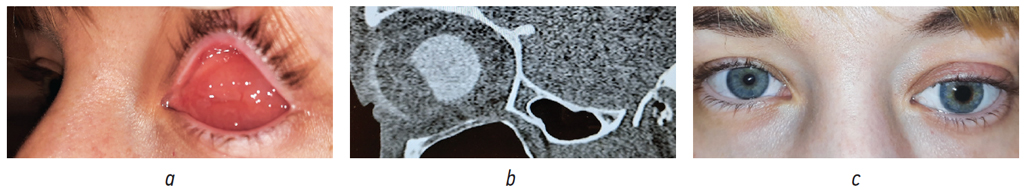

Рис. 11. Пациентка, 33 года: а — общий вид конъюнктивальной полости без протеза. Отёк конъюнктивальной оболочки культи и анофтальмической полости; b — МСКТ-исследование. Гипертрофия мягких тканей кпереди от имплантата с изменённой геометрией. Тонкостенный протез; c — общий вид с протезом. Деформация век, выстояние тонкостенного протеза за счёт гипертрофии и отёка мягких тканей

Fig. 11. Patient, 33 y. o.: a — general view of the conjunctival cavity without prosthesis. Edema of the conjunctiva covering the stump and anophthalmic cavity; b — MSCT study. Soft tissue hypertrophy anterior to the implant with modified geometry. Thin-walled prosthesis. c — general view with prosthesis. Deformation of eyelids, protrusion of a thin-walled prosthesis due to hypertrophy and edema of soft tissues

В-четвертых, на границе изменённого полимера имплантата возникают непредельные связи [20], которые, на наш взгляд, могут проявлять свои токсические свойства, что клинически может быть выявлено в виде асептического воспалительного процесса с гипертрофией мягких тканей глазницы (рис 11, а). Увеличение объёма мягких тканей около опорно-двигательной культи (рис. 11, b) напрямую влияет на качество наружного глазного протезирования и внешний вид пациента (рис. 11, с).